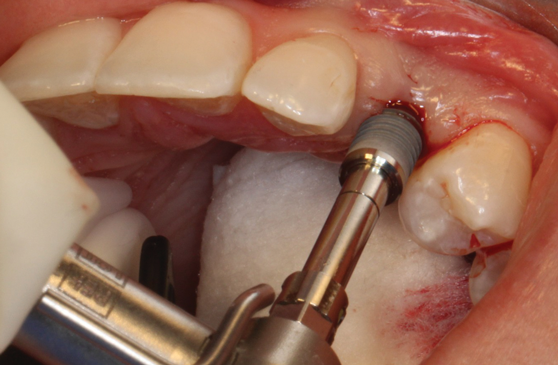

(12.) Placement of an appropriately sized implant into the osteotomy.

Figure 12